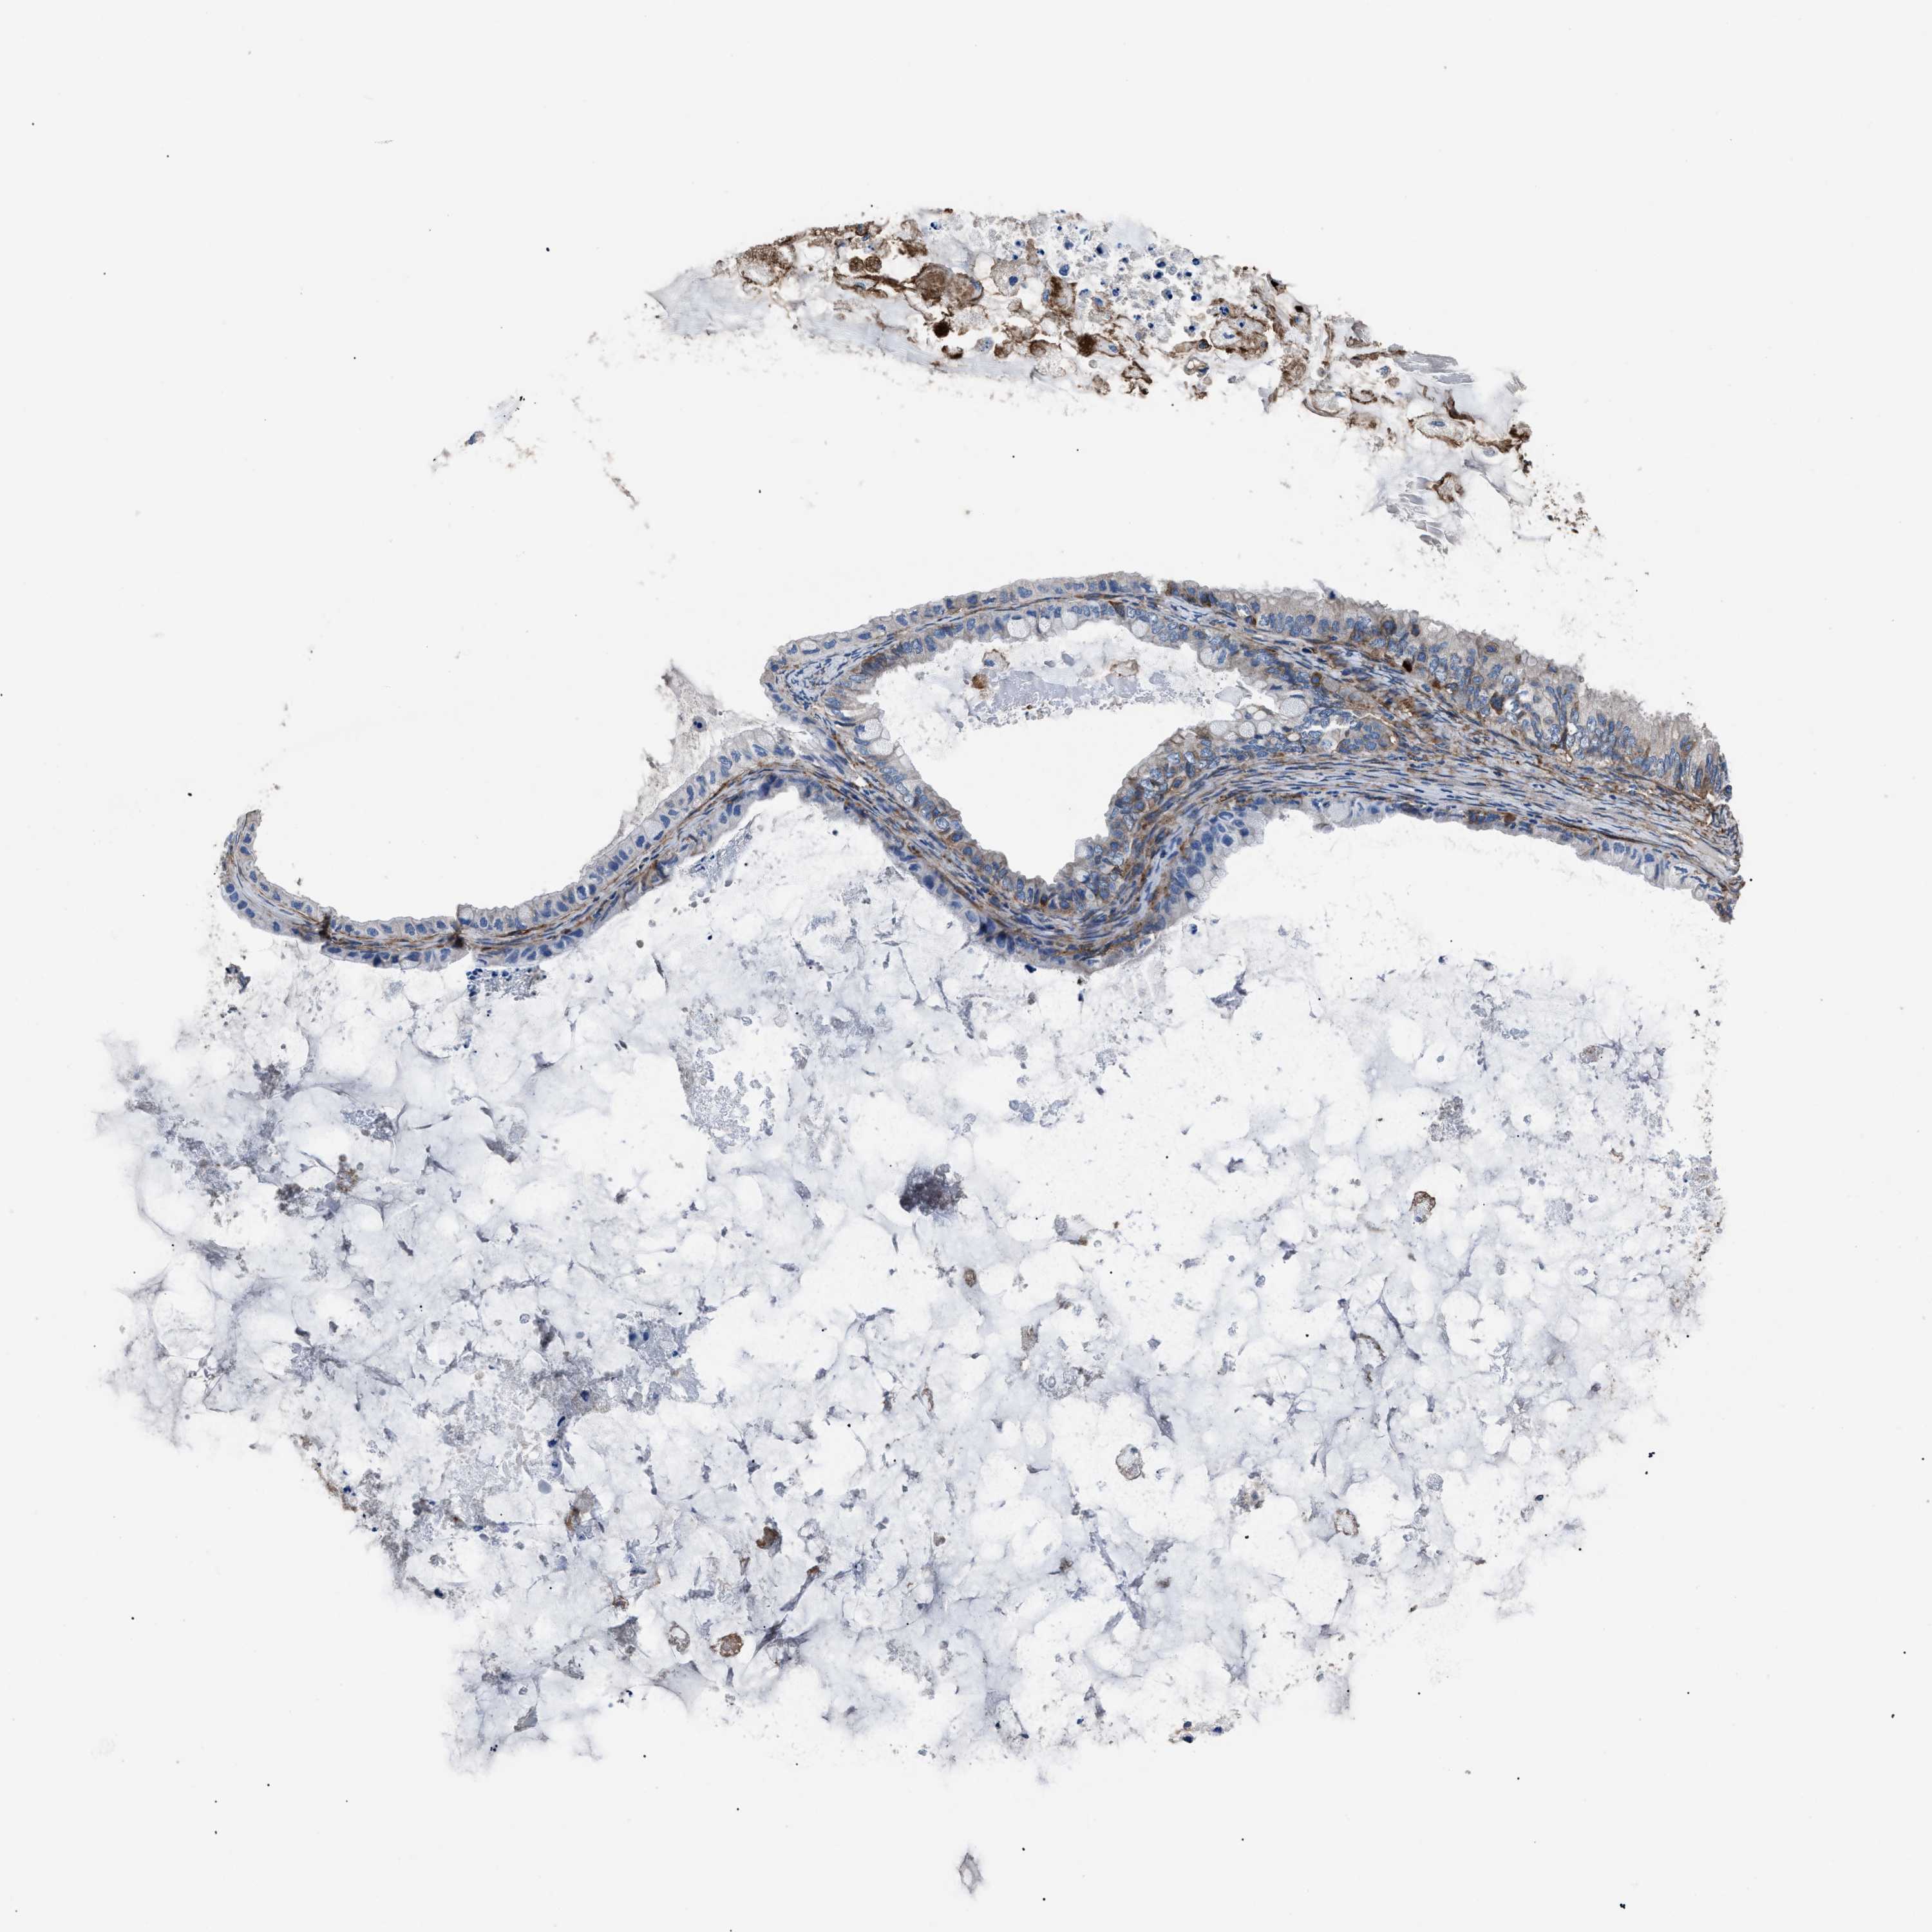

OVARIAN CANCER - Protein expressioni

A mouse-over function shows sample information and annotation data. Click on an image to view it in a full screen mode. Samples can be filtered based on level of antibody staining by selecting one or several of the following categories: high, medium, low and not detected. The assay and annotation is described here.

Note that samples used for immunohistochemistry by the Human Protein Atlas do not correspond to samples in the TCGA dataset.

Antibody stainingi

Antibody staining in the annotated cell types in the current human tissue is reported as not detected, low, medium, or high, based on conventional immunohistochemistry profiling in selected tissues. This score is based on the combination of the staining intensity and fraction of stained cells.

Each image is clickable and will lead to virtual microscopy that enables deeper exploration of all samples and also displays staining intensity scores, fraction scores and subcellular localization as well as patient and tissue information for each sample.

Antibody HPA009285

Antibody HPA017139

Antibody CAB017826

Cystadenocarcinoma, serous, NOS

Carcinoma, endometroid

Cystadenocarcinoma, mucinous, NOS

Carcinoma, NOS